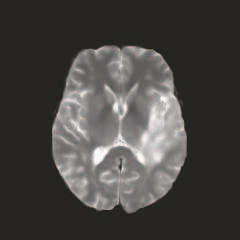

Multi-modal medical image completion has been extensively applied to alleviate the missing modality issue in a wealth of multi-modal diagnostic tasks. However, for most existing synthesis methods, their inferences of missing modalities can collapse into a deterministic mapping from the available ones, ignoring the uncertainties inherent in the cross-modal relationships. Here, we propose the Unified Multi-Modal Conditional Score-based Generative Model (UMM-CSGM) to take advantage of Score-based Generative Model (SGM) in modeling and stochastically sampling a target probability distribution, and further extend SGM to cross-modal conditional synthesis for various missing-modality configurations in a unified framework. Specifically, UMM-CSGM employs a novel multi-in multi-out Conditional Score Network (mm-CSN) to learn a comprehensive set of cross-modal conditional distributions via conditional diffusion and reverse generation in the complete modality space. In this way, the generation process can be accurately conditioned by all available information, and can fit all possible configurations of missing modalities in a single network. Experiments on BraTS19 dataset show that the UMM-CSGM can more reliably synthesize the heterogeneous enhancement and irregular area in tumor-induced lesions for any missing modalities.